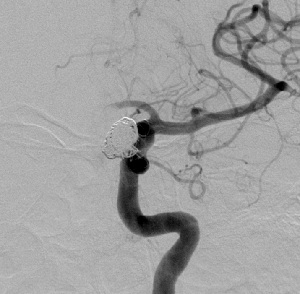

(1) DSA leve unutrašnje karotidne arterije (ACI), pokazuje kompleksnu aneurizmu na C5 segmentu

(2) 3D DSA leve ACI

(3) Implantacija stenta (DSA druga projekcija)

(4) Aneurizma isključena iz cirkulacije koilima

(DSA nakon embolizacije)